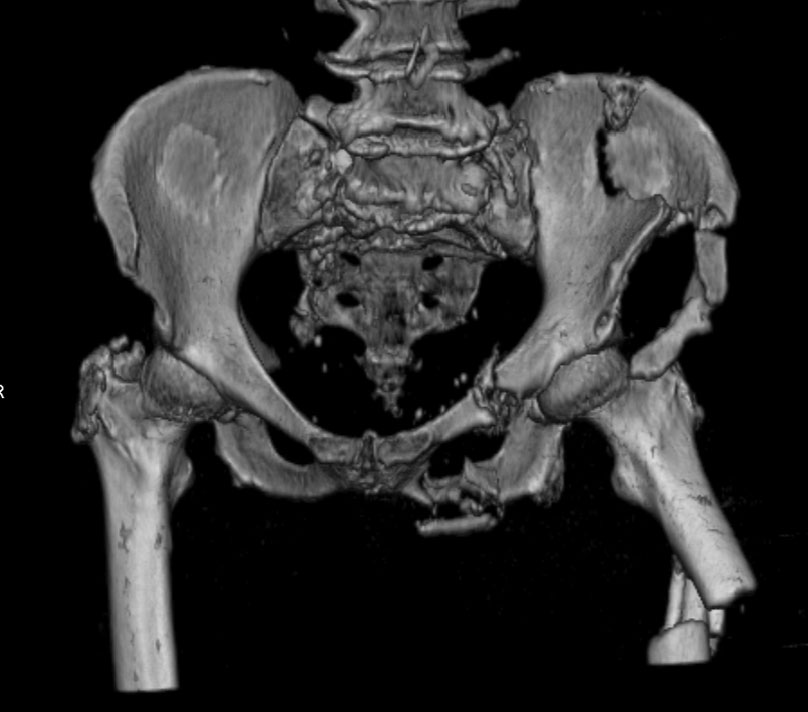

Уважаемые коллеги, в продолжении обсуждения перелома костей таза с отрывами остей досылаю R-снимки (КТ и КТ с 3d реконструкцией)

Имя     : стриганова TB3.jpg